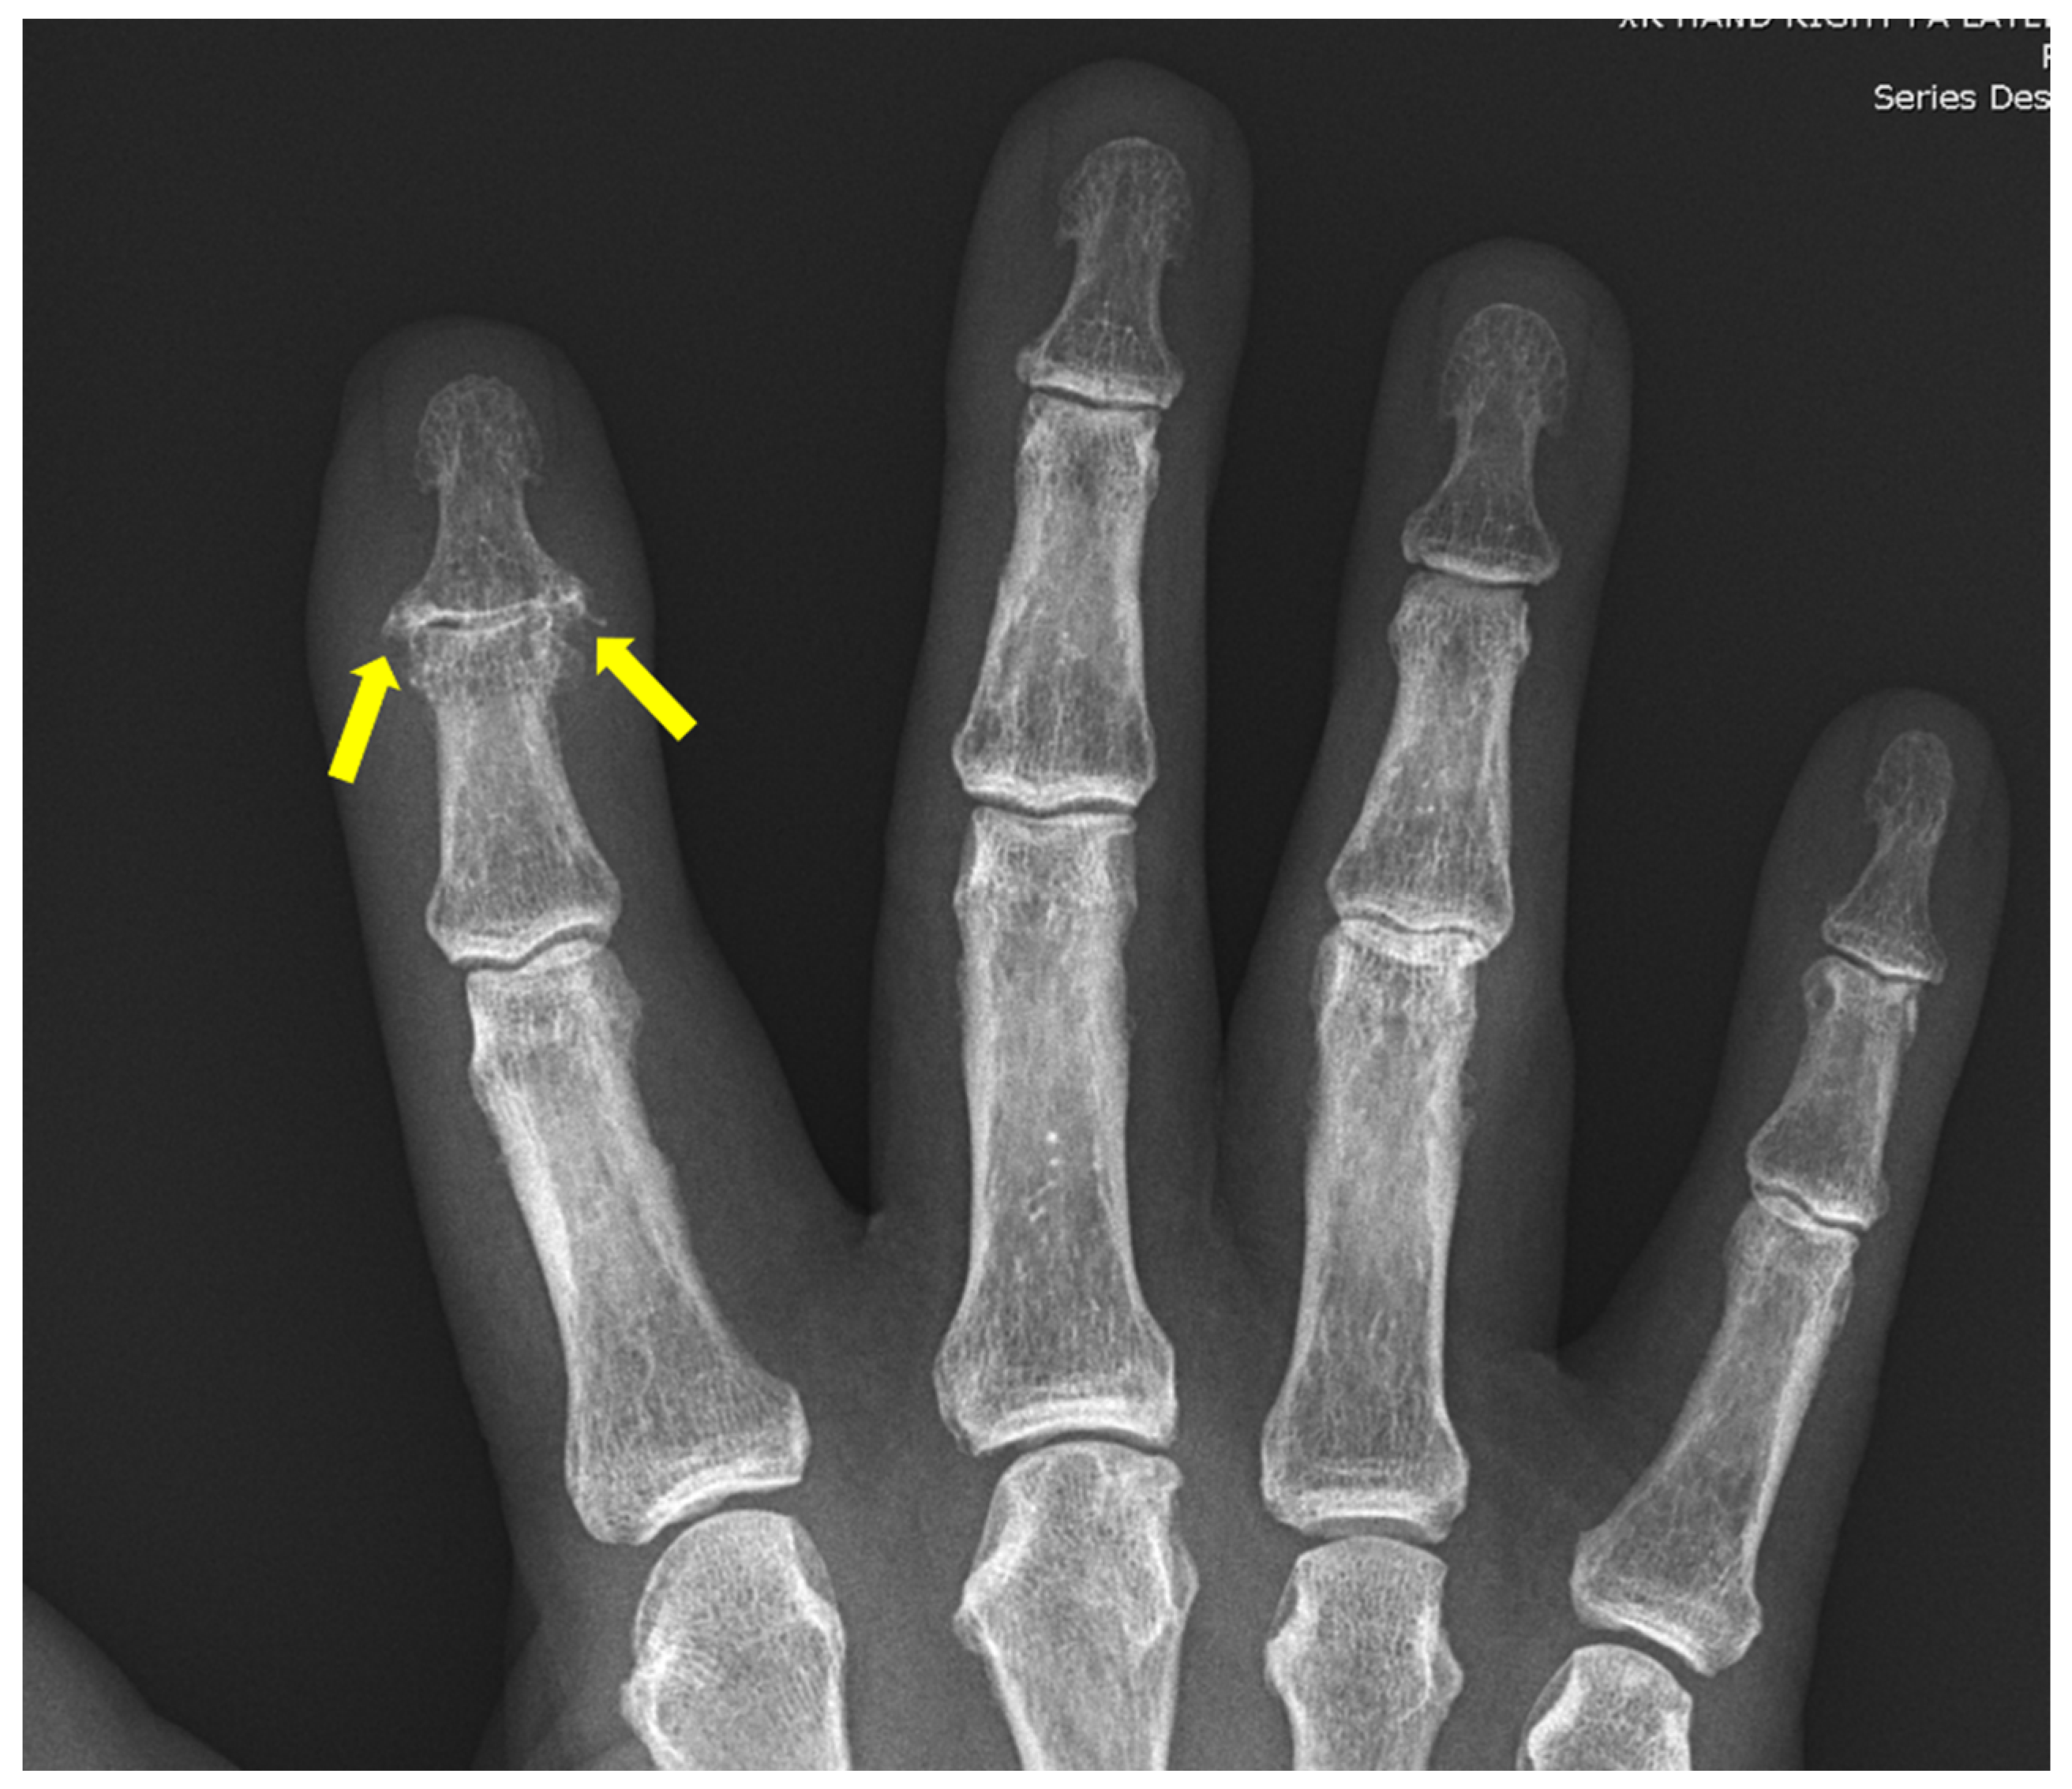

6. Erosive Osteoarthritis

Hallmarks | Sausage-digits Micky-mouse Pencil-in-cup. No osteophyte formation | Gull-wing (not specific, also can be seen in RA and PsA) | More prominent cysts Wrong distribution for primary OA Elbow and shoulders involved Chondrocalcinosis involving the triangular fibrocartilage complex (TFCC), scapholunate and lunotriquetral ligaments | Punched out erosions with overhanging edges | Reducible deformity and subluxations Non-erosive |